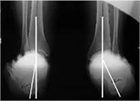

1. 分類は、変形のステージとタイプ分けからなる([1]。ステージは、足変形に可撓性があればⅠ、なければIIとする。変形のタイプはクラスAからクラスEの5つに細分され、クラスは単独あるいは複合することもある(表記例:ⅠA、IIABCIEなど)。(*日本足の外科学会用語委員会による和名)